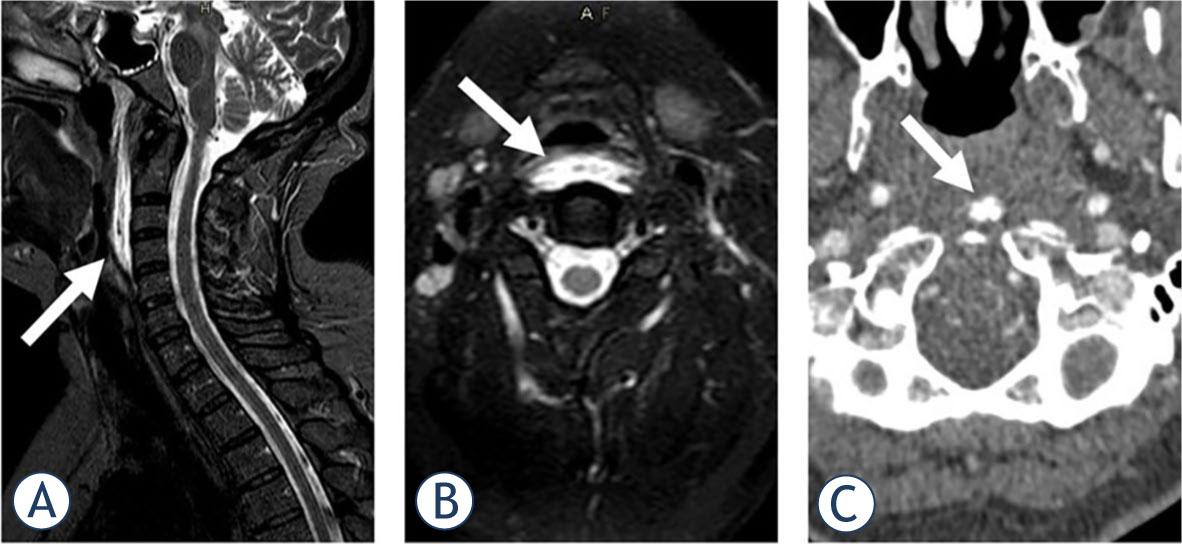

A 51-year-old female with a history of arterial hypertension was referred to the NEU in November 2021 with clinical suspicion of meningitis. Five days prior to referral, she experienced a sudden mild pain in the right posterior neck, radiating to the occipital region. In the following three days, the pain became unbearable. It increased during swallowing and with eye movements. Due to the chronic neck pain, the patient had an MRI of the neck 9 months prior to the examination. Broad-based protrusions of the C5/6 and C6/7 intervertebral discs without compromise of neural structures were described, but no other abnormalities were noted at the time. She was afebrile at presentation. A neurological exam showed limited mobility of the neck and reduced light touch sense over the right lower extremity.

Laboratory workup was normal. Head CT and computed tomography angiography (CTA) of the aortocervical and intracranial vessels revealed no vascular abnormalities. MRI of the cervical spine revealed prevertebral oedema from the C1 to the C4 level (Figure 2), not seen on previous MRIs. In addition, calcifications in front of the C1 arc on CTA was noted. The patient had been treated three days in the hospital and discharged with ibuprofen, 1800 mg daily. The pain gradually subsided over the next two months. The sensory disturbance over the left leg remained unexplained.

STIR (short tau inversion recovery) imaging in sagittal (A) and axial (B) plane demonstrated prevertebral soft tissue swelling and oedema in a 51-year-old female, suggesting retropharyngeal calcific tendinitis as the underlying cause. Calcifications in the medial aspect of the longus colli muscle in front of the C1 arc were noted on computed tomography angiography (CTA) (C), confirming the diagnosis.